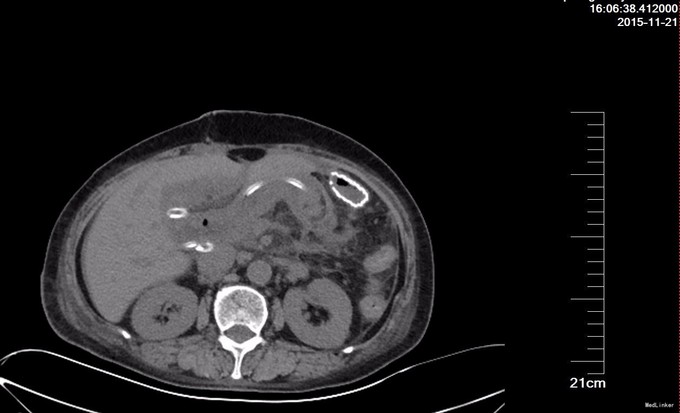

术后复查CT, 胰肠吻合口周围渗出较多,肠壁水肿,肝内胆管多发气体密度影。双侧胸腔可见液性密度影,双肺下叶膨胀不良。术后动态监测引流液淀粉酶,前5天不高,术后7天引流液淀粉酶超过1万,按照2005年国际胰瘘定义研究小组( international study group on pancreatic fistula , ISGPF) 对胰瘘的定义:术后≥3 d 起从手术放置的引流管(或以后放置的引流管或经皮穿刺引流) 中引出淀粉酶大于正常血清淀粉酶水平3 倍的液体且引流量可计,本例属于胰瘘。胰瘘既可以是胰肠吻合口瘘,也可以是来源于胰腺实质的与吻合口无关的渗漏,进一步经引流管造影,发现肠粘膜显影,提示胰肠吻合口瘘。胰瘘分为无临床症状的A级胰瘘,临床相关的B级胰瘘,导致病人腹痛、发热或血中性粒细胞升高,需要使用抗生素、全胃肠外营养(TPN)或生长抑素等治疗,还有威胁生命的C级胰瘘,需要积极使用抗生素、TPN或生长抑素,甚至需要手术或转入重症监护病房,也可能术后死亡,本病例属于最轻的A级胰瘘。胰腺术后总体胰瘘发生率20-40%,胰体尾切除后胰瘘发生率高于胰头切除术后。本例虽发生胰瘘,但是症状轻,最终术后3周愈合,拔管出院。